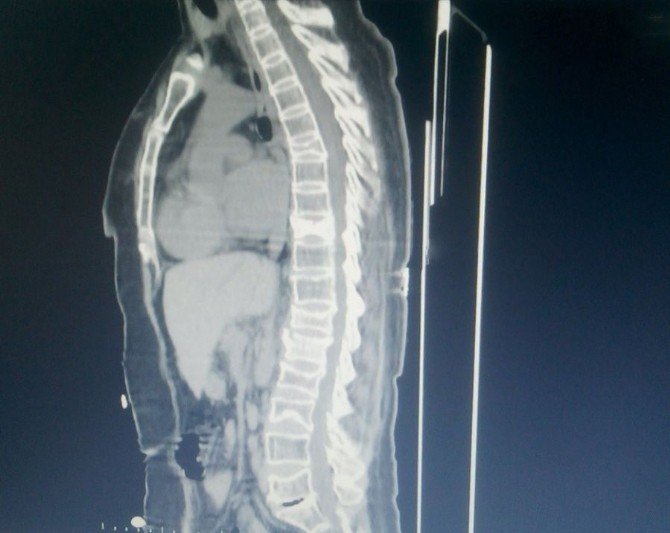

"Hasta bana geldiğinde ayağa kalkmada ve yürümede çok zorlanıyor ve ayakta dik olarak duramıyordu. Yapılan tomografi ve mr sonucunda t6, t9, t12, l1, l2, l3 omurga kemiklerinde çökme ve patlama kırıkları olduğunu gördük. Hastaya operasyonla sırt (torakal) ve bel (lomber) omurgalarına titanyum vida ve plak sistemi ile yeni bir omurga desteği sağlayacağımızı karalaştırdık. Kemik erimesinin ileri derecede olması sırt omurgalarını başlangıcından vida işleminin yapılacağından ileri derecede riskli olduğu aşikardır. Bu durumlarda çok ender olarak operasyon kararı alınabilmektedir. Operasyon 3 saat sürdü. Hastaya 26 titanyum vida ile prod sistemiyle yeni bir omurga desteği sağlayarak hastanın ayakta durmasını ve yürümesini sağlayan yeni bir iskelet destek sistemi oluşturduk. Operasyondan sonraki 3. gününde hastayı yürüttük. Hastanın ve ailenin mutluluğu görülmeye değerdi. 4. günü hastayı taburcu ettim. Tabi henüz her şey bitmedi. Yaranın iyileşmesi ve uygulanan platin ve vidaların kemikle kaynaşması için en az 3 aylık bir zamana daha ihtiyacımız var. Hasta tedavimiz altında ve kontrolümüzde kalmaya devam ediyor."